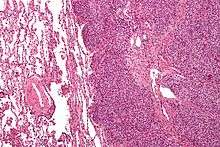

| Micrograph of metastatic Ewing sarcoma (right of image) in normal lung (left of image). PAS stain. | |

The definitive diagnosis is based on histomorphologic findings, immunohistochemistry and molecular pathology.

Ewing's sarcoma is a small-blue-round-cell tumor that typically has a clear cytoplasm on H&E staining, due to glycogen. The presence of the glycogen can be demonstrated with positive PAS staining and negative PAS diastase staining. The characteristic immunostain is CD99, which diffusely marks the cell membrane. Morphologic and immunohistochemical findings are corroborated with an associated chromosomal translocation, of which several occur. The most common translocation, present in about 90% of Ewing sarcoma cases, is t(11;22)(q24;q12),[12][13] which generates an aberrant transcription factor through fusion of the EWSR1 gene with the FLI1 gene.[14]

The pathologic differential diagnosis is the grouping of small-blue-round-cell tumors, which includes lymphoma, alveolar rhabdomyosarcoma, and desmoplastic small round cell tumor, among others.